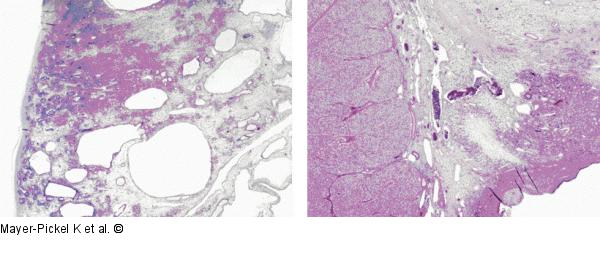

Abbildung 2a-b: Krukenberg-Tumor Krukenberg-Tumor des rechten Ovars, ausgehend von einem niedrig differenzierten Adenokarzinom |

Krukenberg-Tumor des rechten Ovars, ausgehend von einem niedrig differenzierten Adenokarzinom |